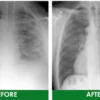

In an extensive global clinical trial spanning 28 days with 2,738 participants, Respira™ Lung Care Spray demonstrated remarkable efficacy in purifying and revitalizing the lungs of those with histories of smoking or dust exposure. Participants reported significant enhancements in symptoms, including cough, breathlessness, phlegm production, chest discomfort, and breathing challenges.

In an extensive global clinical trial spanning 28 days with 2,738 participants, Respira™ Lung Care Spray demonstrated remarkable efficacy in purifying and revitalizing the lungs of those with histories of smoking or dust exposure. Participants reported significant enhancements in symptoms, including cough, breathlessness, phlegm production, chest discomfort, and breathing challenges.

“A noteworthy finding from the CT scans conducted before and after the study was a substantial reduction of lung residues in participants, reaching an almost imperceptible level with an impressive reduction rate of 99.94%.,” says Dr. Vogel.